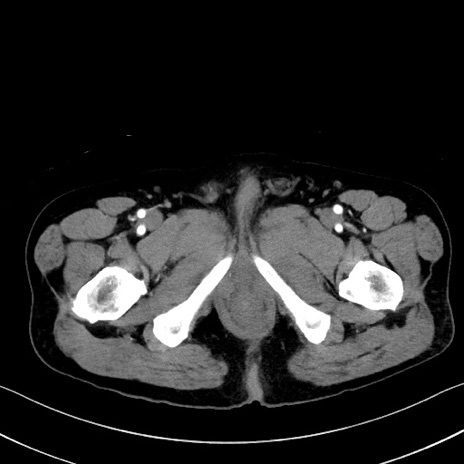

症例35(横断像)

【症例】70歳代 男性

【主訴】腹部膨満、嘔吐

【現病歴】昨日より腹部膨満感出現。本日増悪し、仙痛出現。嘔吐あり、受診。

【既往歴】糖尿病、胆摘後

【身体所見】BP 149/80mmHg、HR 74/min、BT 35.9℃、腹部:膨満、軟、圧痛なし。腸雑音減弱あり。上腹部正中切開瘢痕あり。

【データ】WBC 13500、CRP 1.72